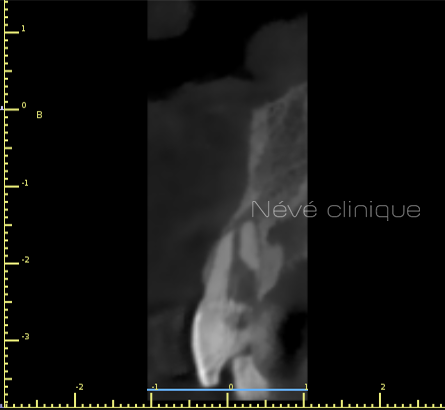

Lors de la consultation pré-implantaire, nous positionnons virtuellement les implants sur un logiciel de planification spécifique. Nous enregistrons votre image radiographique 3D (cone beam) et l’empreinte numérique de vos mâchoires dans ce logiciel.